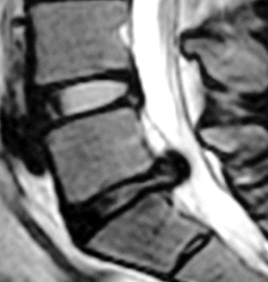

| 腰椎椎間板ヘルニアの手術前 | 腰椎椎間板ヘルニアの手術後 | 顕微鏡下にヘルニアを摘出 | |